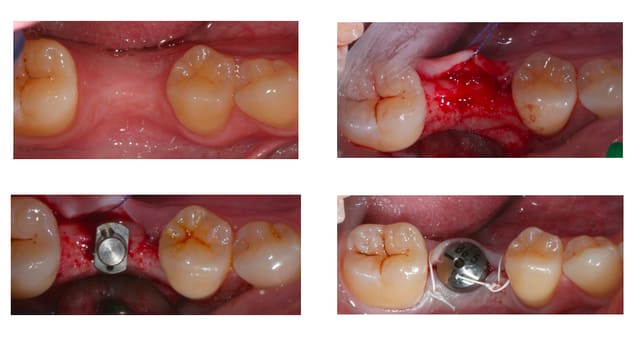

Bon je m'y colle, c'est pas le même niveau qu'olivier, mais ce sujet étant censé être pour les débutants je poste.

Patient 26 ans, à qui il manque 46, 25 et 26.

Pour l'instant je vous propose la partie préparation et mise en place de l'implant en 46, la suite peut être bientôt.

Dans l'ordre si le site veut bien, wax-up ( cirage pour céramik ;) ) , guide radio, et scan.

Photos pré-op, indicateur de direction en place et post-op.

Il s'agit d'un implant astra osseospeed de 5 mm de diamètre et 9 de long.

Prothèse prévue à 6 semaines.